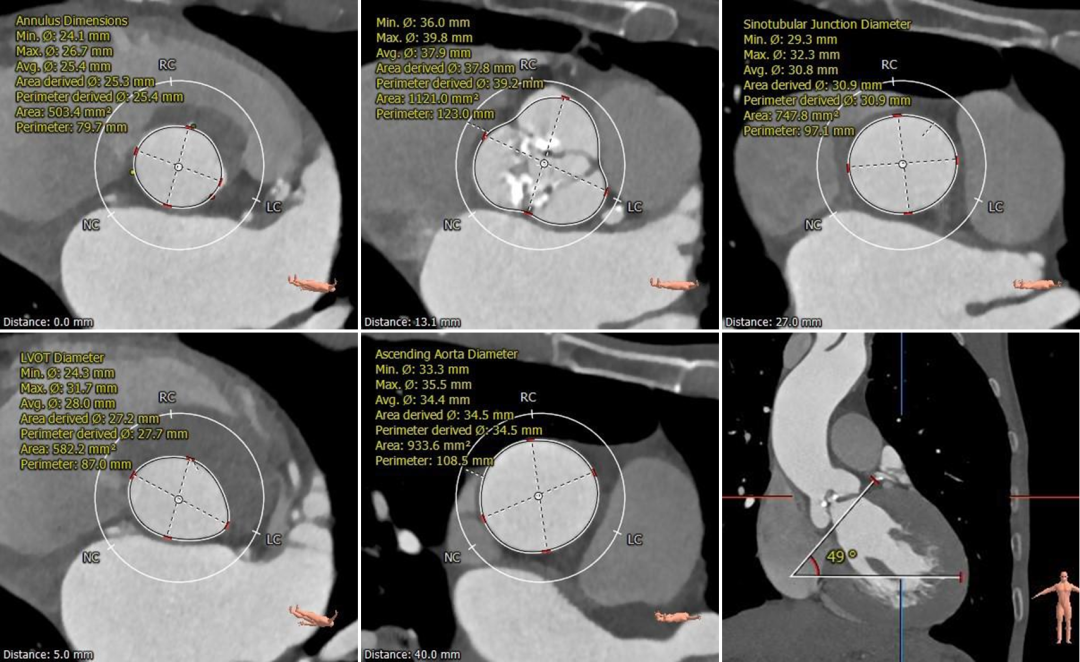

根部测量

瓣环平均径25.4mm,瓦氏窦、STJ、升主内径可,非横位心

冠脉测量

冠脉开口高度可,切线位测量未见冗长瓣叶

瓣环平均径22.2mm,瓦氏窦、STJ、升主内径略小,非横位心

冠脉开口高度可,切线角度测量,

左窦瓣叶长于LCA开口到瓣叶根部距离